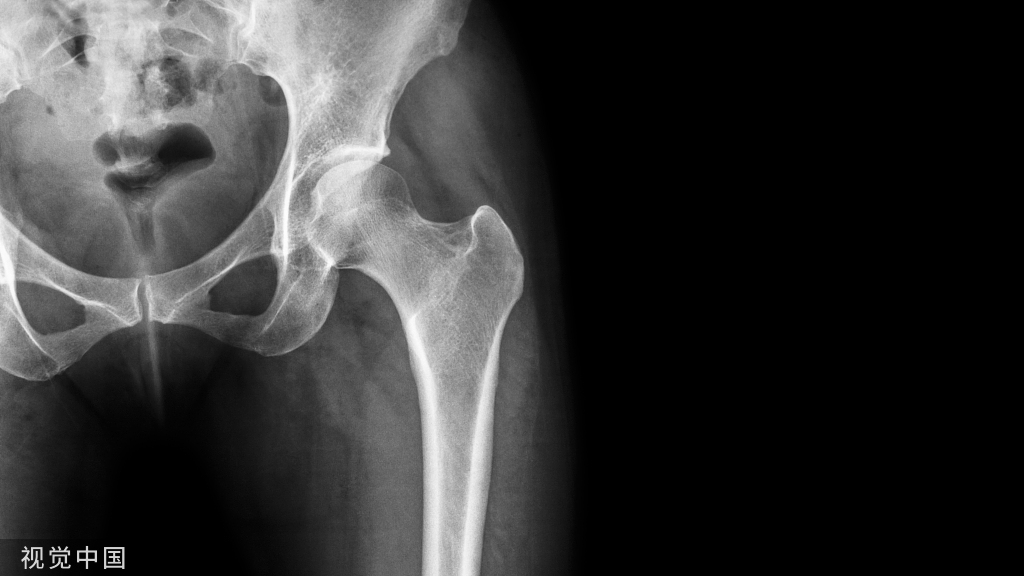

② 髋关节

病例4股骨颈骨折,在CT横断面骨窗上未见明显液体分层(a),在软组织窗(b)可见高密度血肿影(箭头所示,CT值为50HU)。